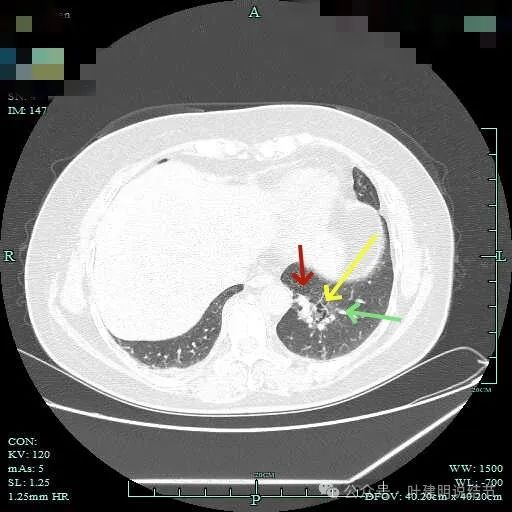

病灶轮廓欠清,较为散在,缺乏聚拢性,似乎有些像斑点状。

有少许磨玻璃成分出现,较前面层面整体轮廓显得清楚点。

到这层面,聚拢性较前明显,密度显杂乱。